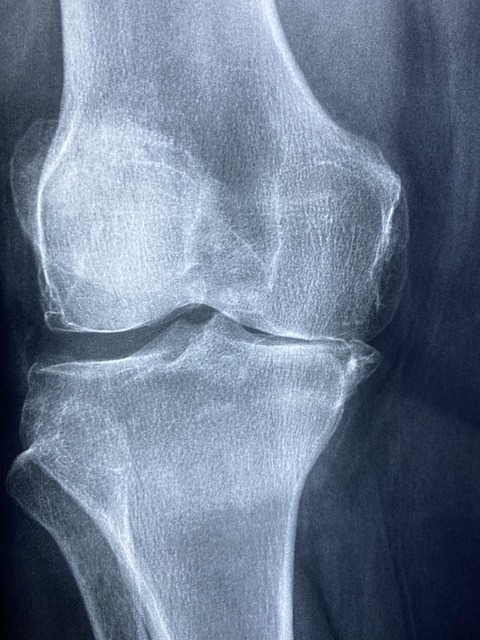

MSM 효능 중 가장 잘 알려진 것은 바로 관절 건강입니다. MSM은 연골의 주요 구성 성분 중 하나인 콜라겐 합성을 촉진하고, 염증 반응을 억제해 관절 통증을 완화합니다. 특히 무릎, 어깨, 손목 관절이 자주 아픈 중장년층에게 도움이 됩니다. 미국 임상영양학 저널(Journal of Clinical Nutrition)에 따르면 MSM을 12주간 복용한 그룹에서 관절 통증이 유의미하게 감소했다는 결과가 발표되었습니다.